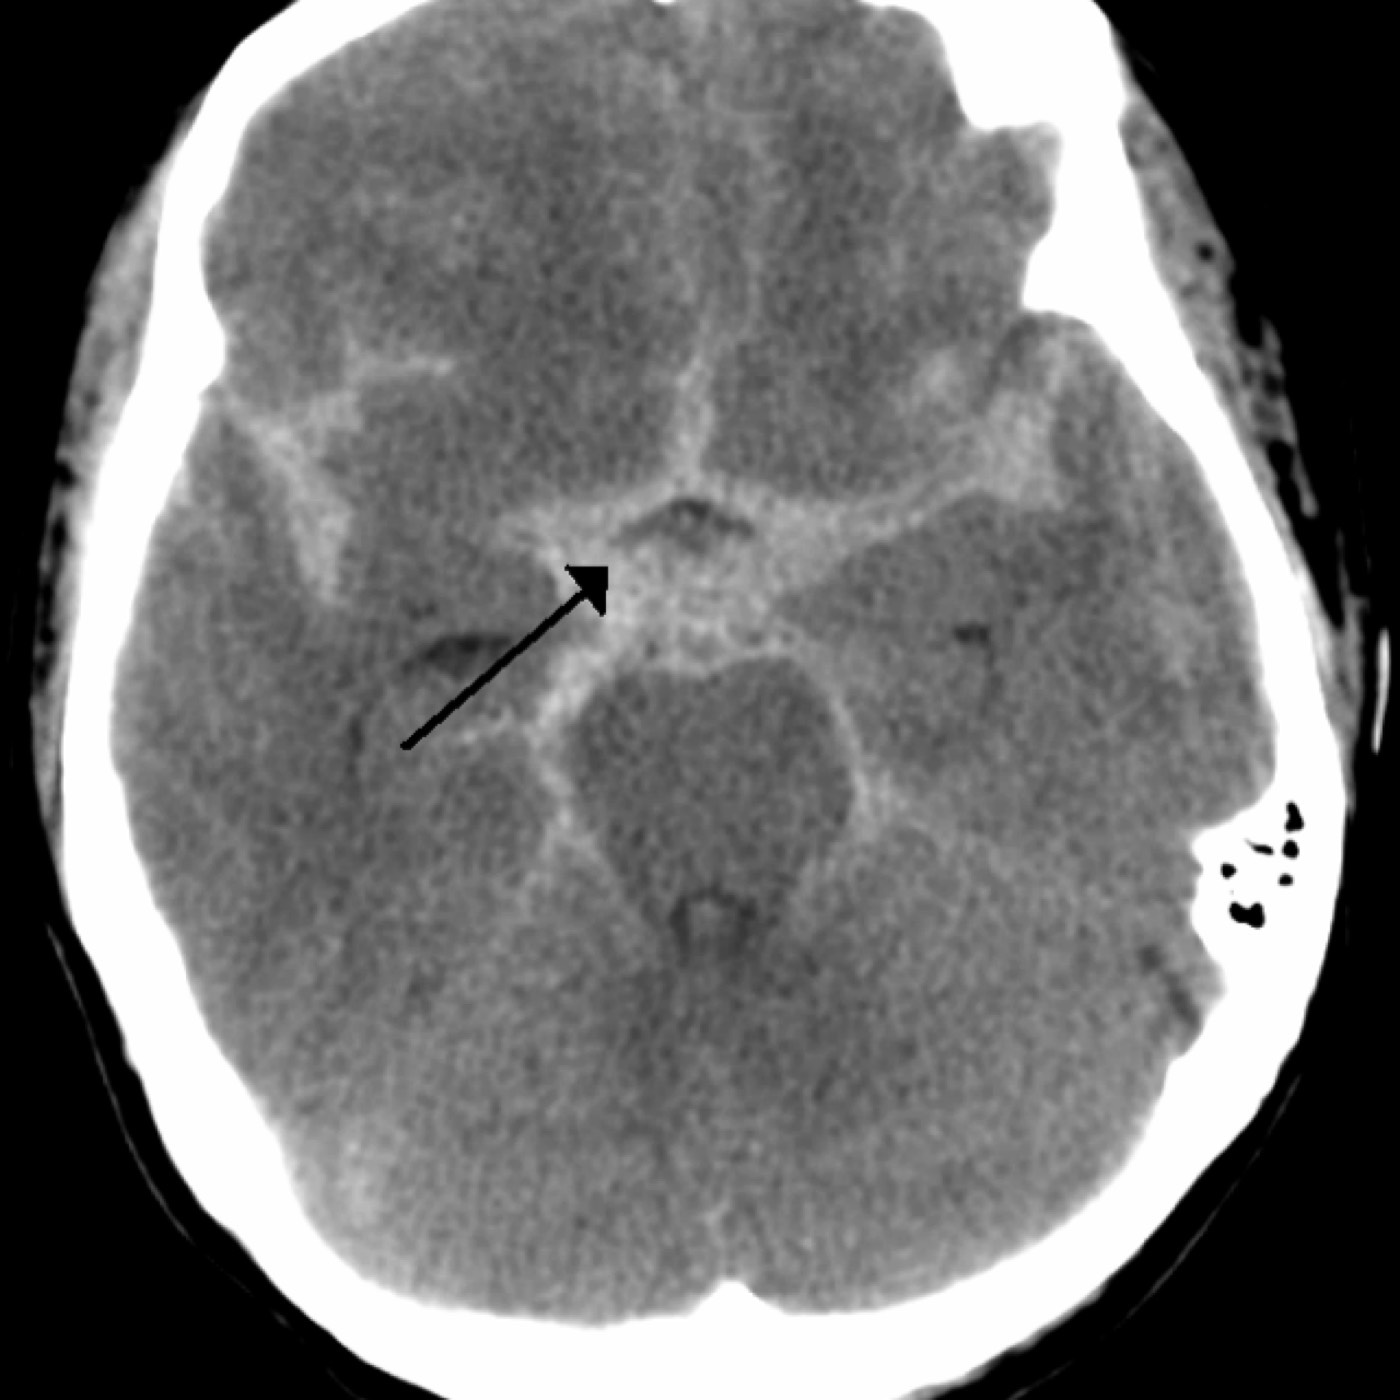

Contributor: Aaron Lessen, MD Educational Pearls: Traumatic Brain Injuries are a frequent complaint in the Emergency Department and have increased in recent years. The American Association for Surgery of Trauma (AAST) has created Brain Injury Guidelines (BIG), in an attempt to categorize brain injuries and the level of treatment they require. They are… BIG 1 Normal neuro exam Not intoxicated Not on anticoagulation or antiplatelet medications Minimal findings on head CT No fracture Maximum of "trace" subarachnoid hemorrhage No intraventricular hemorrhage Monitor for 6 hours No need to repeat the head CT No need to consult neurosurgery BIG 2 Normal neuro exam Not on anticoagulation or antiplatelet medications Any of the following Intoxicated Slightly more findings on head CT Non-displaced skull fracture 4-8 mm bleed (subdural, epidural, intraparenchymal (max two locations)) Maximum of "localized" subarachnoid hemorrhage No intraventricular hemorrhage Hospitalize No need to transfer No need to repeat the head CT No need to consult neurosurgery BIG 3 Abnormal neuro exam On anticoagulation or antiplatelet medications Intoxicated Significant findings on head CT Displaced skull fracture >8 mm bleed (subdural, epidural, intraparenchymal (or more than 2 locations)) "Scattered" subarachnoid hemorrhage Intraventricular hemorrhage Full treatment, admission to trauma center, neurosurgery evaluation References Joseph B, Friese RS, Sadoun M, Aziz H, Kulvatunyou N, Pandit V, Wynne J, Tang A, O'Keeffe T, Rhee P. The BIG (brain injury guidelines) project: defining the management of traumatic brain injury by acute care surgeons. J Trauma Acute Care Surg. 2014 Apr;76(4):965-9. doi: 10.1097/TA.0000000000000161. PMID: 24662858. Joseph B, Obaid O, Dultz L, Black G, Campbell M, Berndtson AE, Costantini T, Kerwin A, Skarupa D, Burruss S, Delgado L, Gomez M, Mederos DR, Winfield R, Cullinane D; AAST BIG Multi-institutional Study Group. Validating the Brain Injury Guidelines: Results of an American Association for the Surgery of Trauma prospective multi-institutional trial. J Trauma Acute Care Surg. 2022 Aug 1;93(2):157-165. doi: 10.1097/TA.0000000000003554. Epub 2022 Mar 28. PMID: 35343931. Summarized by Jeffrey Olson, MS4 | Edited by Jeffrey Olson and Jorge Chalit, OMS4 Donate: https://emergencymedicalminute.org/donate/